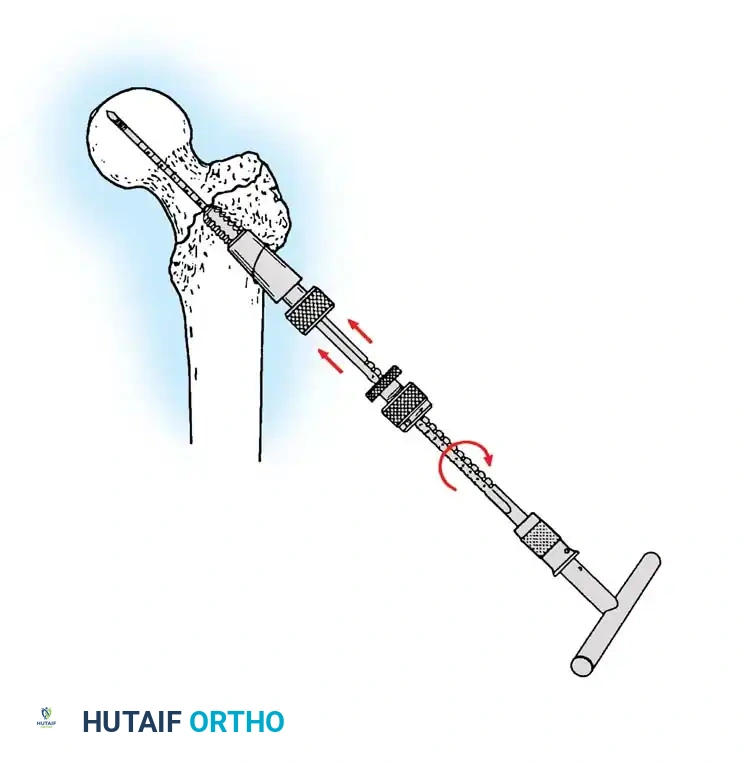

If a cephalomedullary nail is chosen, the entry point is established at the tip of the greater trochanter (or slightly medial, depending on the specific implant design).

Insertion of the cephalomedullary nail down the femoral shaft. Care must be taken not to distract the fracture site during insertion.

After the nail is seated, the proximal lag screw(s) are inserted through the nail into the femoral head, adhering to the same TAD principles.

Proximal locking of the cephalomedullary nail. The targeting guide ensures accurate trajectory into the femoral neck.